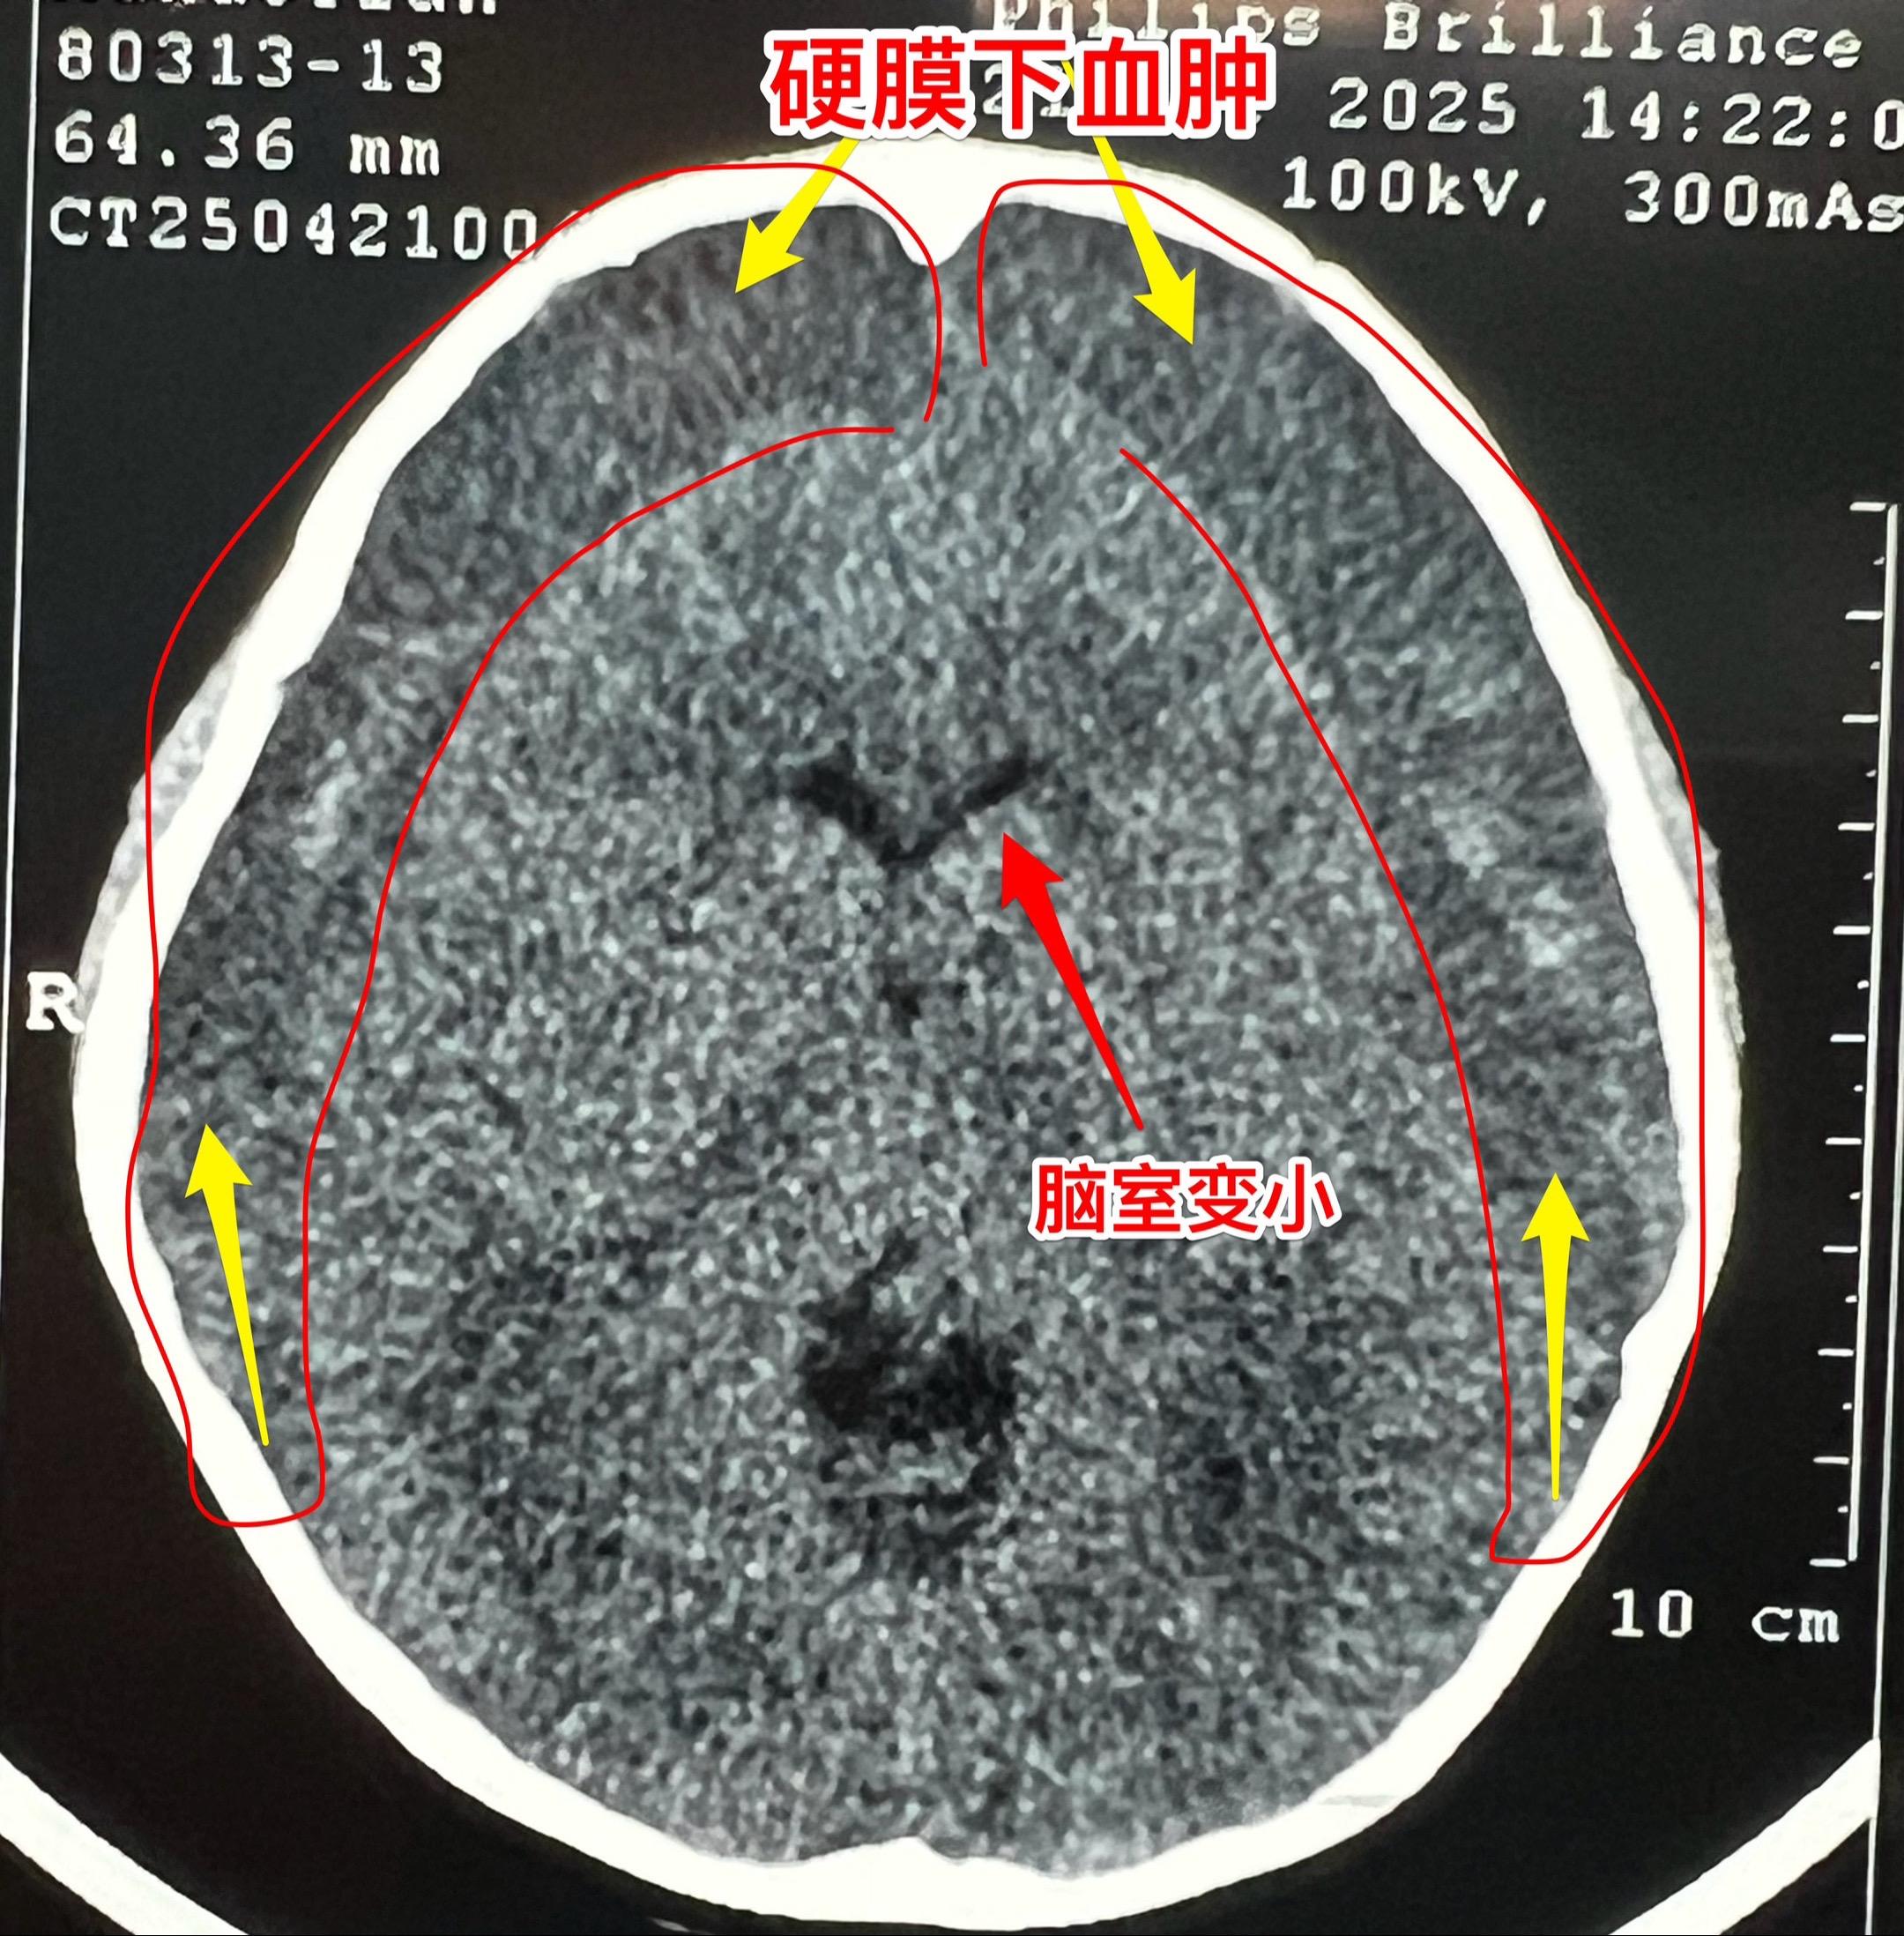

五岁男孩子双侧慢性硬膜下血肿。这个五岁男孩子,五个月前曾经在我科行颅咽管瘤切除手术。 颅咽管瘤切除后顺利出院。出院后三个月复查磁共振显示双侧脑部有硬膜下积液,逐步转为硬膜下血肿。小孩子没有头痛症状,家长发现小孩子行走步态不太正常,不像以前那样灵活。当时就打算给患儿作硬膜下血肿引流术。但是患儿因为感染病毒发烧,手术只好推迟。 4月25日给患儿作了硬膜下血肿引流手术。这个手术在我科属于很简单的手术。预计五一假期前就可以出院了。